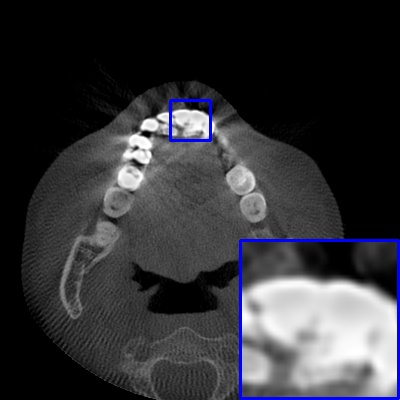

Figure 3: Visual comparison of MAR images by different methods on synthetic MA image. The PSNR (dB)/SSIM results are reported below each image for reference.

Results on synthetic MAR. In Table 1, we provide the quantitative results. One can see that our MARformer-L outperforms the other methods in terms of PSNR and SSIM, but needs only 11.76M parameters and 60.25G FLOPs. Note that the second best method Uformer-B has 50.42M parameters and 205.82G FLOPs. Besides, our MARformer-T achieves similar PSNR and SSIM results with Uformer-T, but needs only 0.40M parameters and 12.82G FLOPs compared to 5.24M and 25.39G for Uformer-T. Our MARformers also achieves faster inference speeds than the Uformers, though with inferior Dice scores, respectively. The qualitative results of visual quality are presented in Fig. 3. We observe that our MARformer-L well recovers the teeth shapes and obtains higher PSNR and SSIM results than the other comparison methods. The light-weight MARformer-L achieves similar results to Uformer-T. All these results validate that our MARformer is more efficient than the comparison methods on dental CBCT MAR.